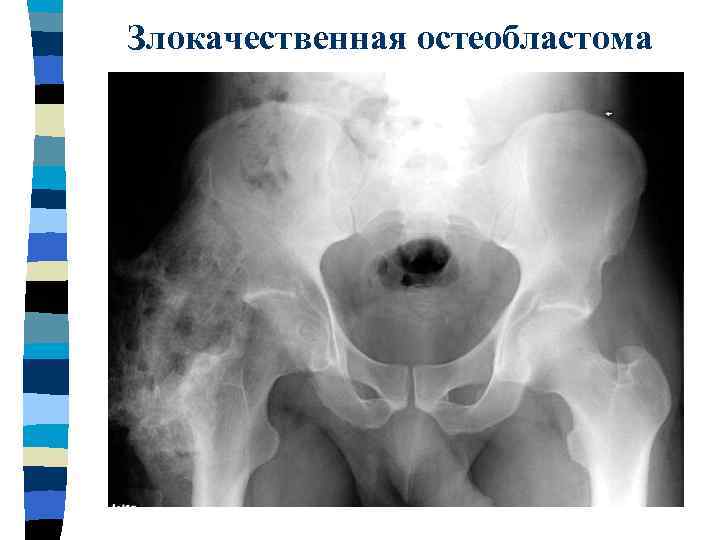

Злокачественная остеобластома